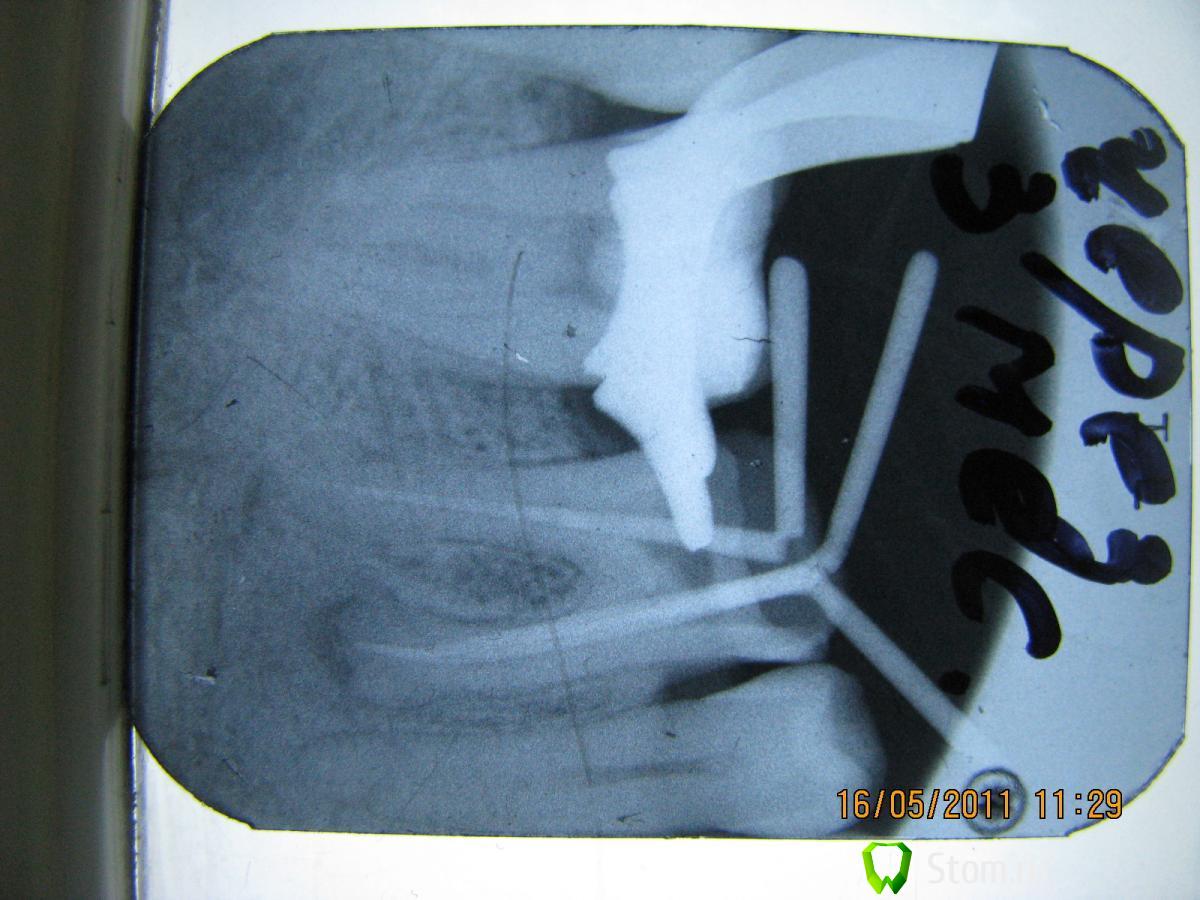

Elenushka Опубликовано 13 января, 2012 Автор Поделиться Опубликовано 13 января, 2012 Вот представляю вашему вниманию пациента.На зубах 45- 47 с 1994 года по 2010г находился металло-керамический мост. НИчего его не беспокоило. Пришел с целью заменить конструкции.(сразу оговорка- он категорически против удаления зубов, денег на эксперименты не жалеет)))Сделала снимок и увидела- перфор, сделанный давным давно,кости как- то маловато. Ну вообщем предлагала удалить, ни в какую. Он мой хороший знакомый, поэтому принялись экспериментировать. 47зуб- был под вкладкой много лет не стали трогать. Вообщем в одно вмешательство- откинут слизисто- надкостничный лоскут, все зачищено, перфор отпрепарирован. Закрыт цементом. Дефект заполнен костью,прикрыт мембраной. Все ушито. следующий снимок сделан совсем недавно( спустя чуть больше 10 месяцев. Запротезирован( мк мост с круговой гирляндой) Снимок работы позже(он в отъезде).В общем на снимочке все так себе вроде бы, а во рту все очень прилично выглядит. Ссылка на комментарий

ger_berra Опубликовано 14 января, 2012 Поделиться Опубликовано 14 января, 2012 Вот представляю вашему вниманию пациента.На зубах 45- 47 с 1994 года по 2010г находился металло-керамический мост. НИчего его не беспокоило. Пришел с целью заменить конструкции.(сразу оговорка- он категорически против удаления зубов, денег на эксперименты не жалеет)))Сделала снимок и увидела- перфор, сделанный давным давно,кости как- то маловато. Ну вообщем предлагала удалить, ни в какую. Он мой хороший знакомый, поэтому принялись экспериментировать. 47зуб- был под вкладкой много лет не стали трогать. Вообщем в одно вмешательство- откинут слизисто- надкостничный лоскут, все зачищено, перфор отпрепарирован. Закрыт цементом. Дефект заполнен костью,прикрыт мембраной. Все ушито. следующий снимок сделан совсем недавно( спустя чуть больше 10 месяцев. Запротезирован( мк мост с круговой гирляндой) Снимок работы позже(он в отъезде).В общем на снимочке все так себе вроде бы, а во рту все очень прилично выглядит. Мне бы совесть не позволила так эксперементировать 1 Ссылка на комментарий